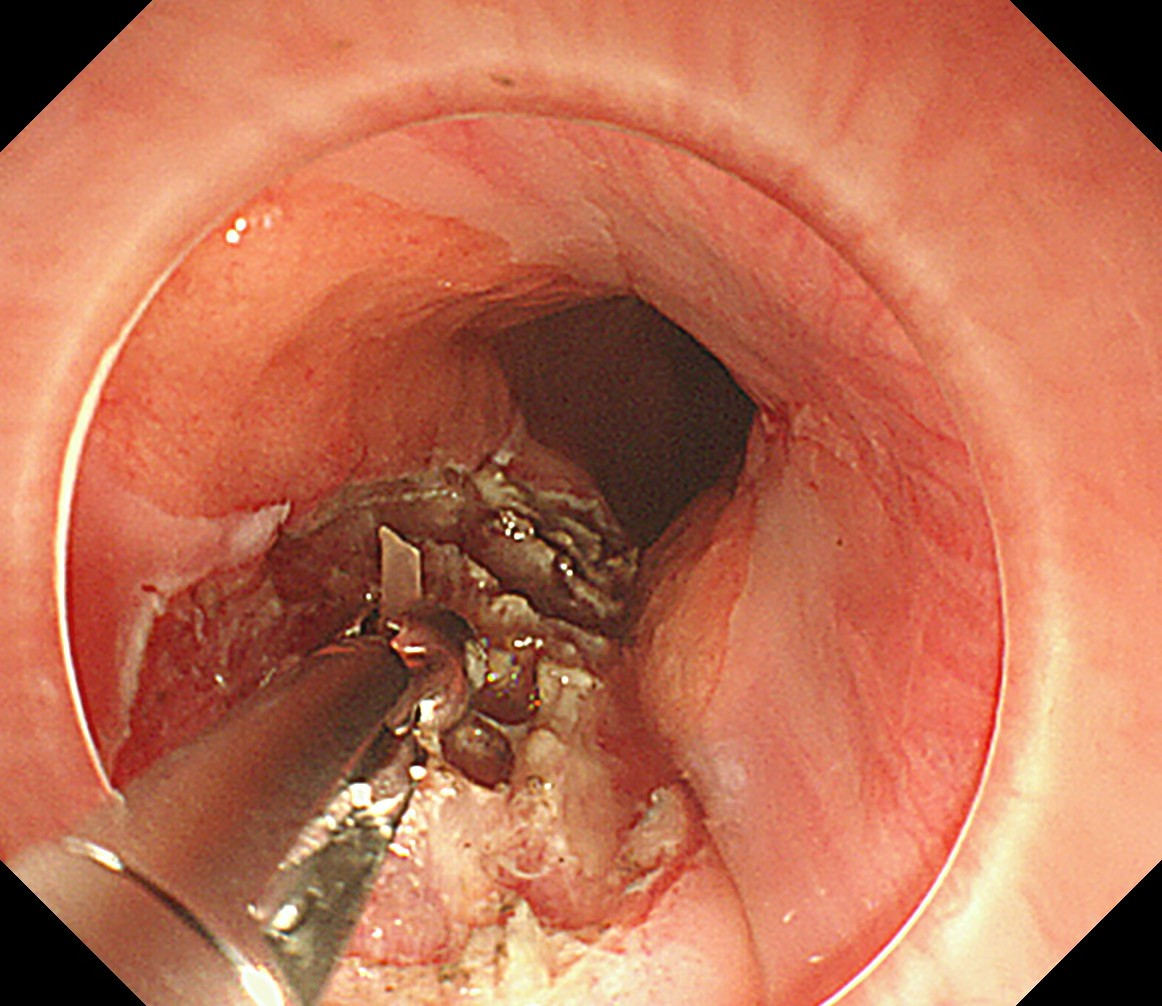

拔出异物的过程

手术台上,刘蔚先小心翼翼切开脓肿处的食管黏膜,大量黄色脓液瞬间涌出,先为食管“排脓减压”;随后逐层探查,黏膜下层翻找无果,便屏住呼吸,在毫厘之间轻轻切开固有肌层,目光紧紧锁定视野,在与肌肉颜色近乎一致的地方,终于发现了那根“藏猫猫”的鱼刺!刘蔚轻夹鱼刺,慢慢提拉,生怕稍一用力刺破食管壁,这根长度1.5厘米的鱼刺,终于被成功取出,与CT报告完全吻合。

普通鱼刺卡喉,医生几十秒到两三分钟便能取出,而这次,整个手术用了将近一个小时,远比常规取刺艰难百倍,医生在几毫米厚的食管壁里层层翻找,每一次下刀、每一次探查,都是对技术和耐心的极致考验。